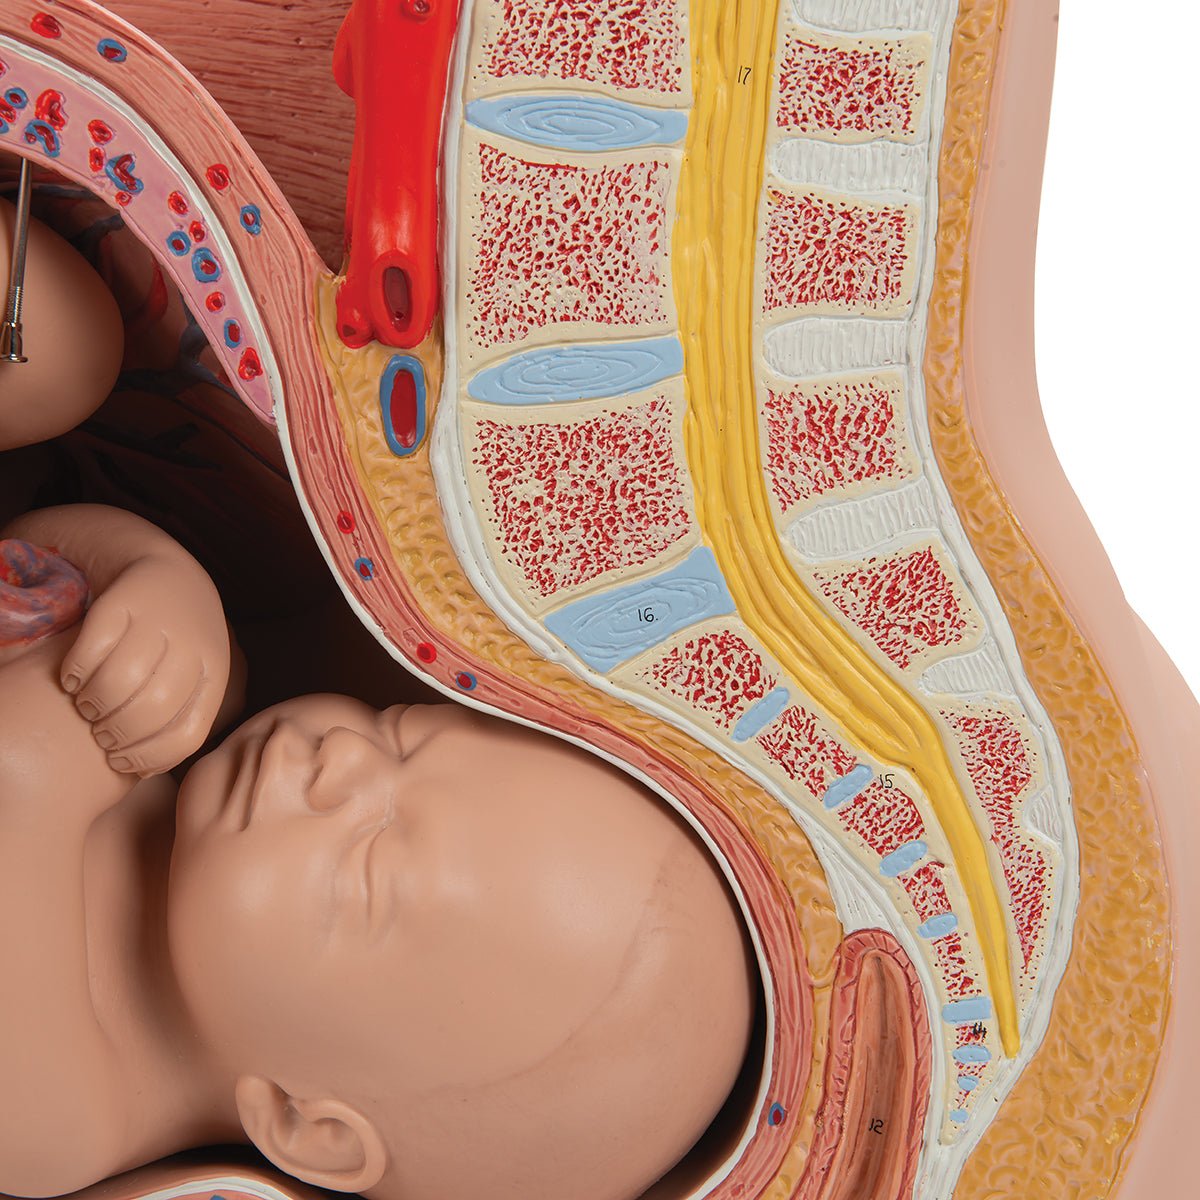

Selling anatomical models is the mainstay of eAnatomi, although we also spend a lot of resources developing our own anatomical materials such as posters. Anatomical models are used for various purposes and can show both defined tissues, organs and organ systems. Are you looking for a simple model of bone tissue or perhaps an advanced torso model based on MRI technology, you can find it all at eanatomi.com.